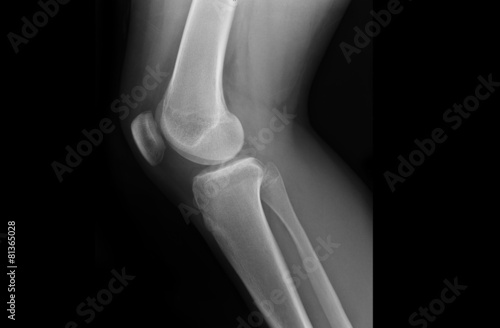

Рентген при смещении коленной чашечки: что нужно знать